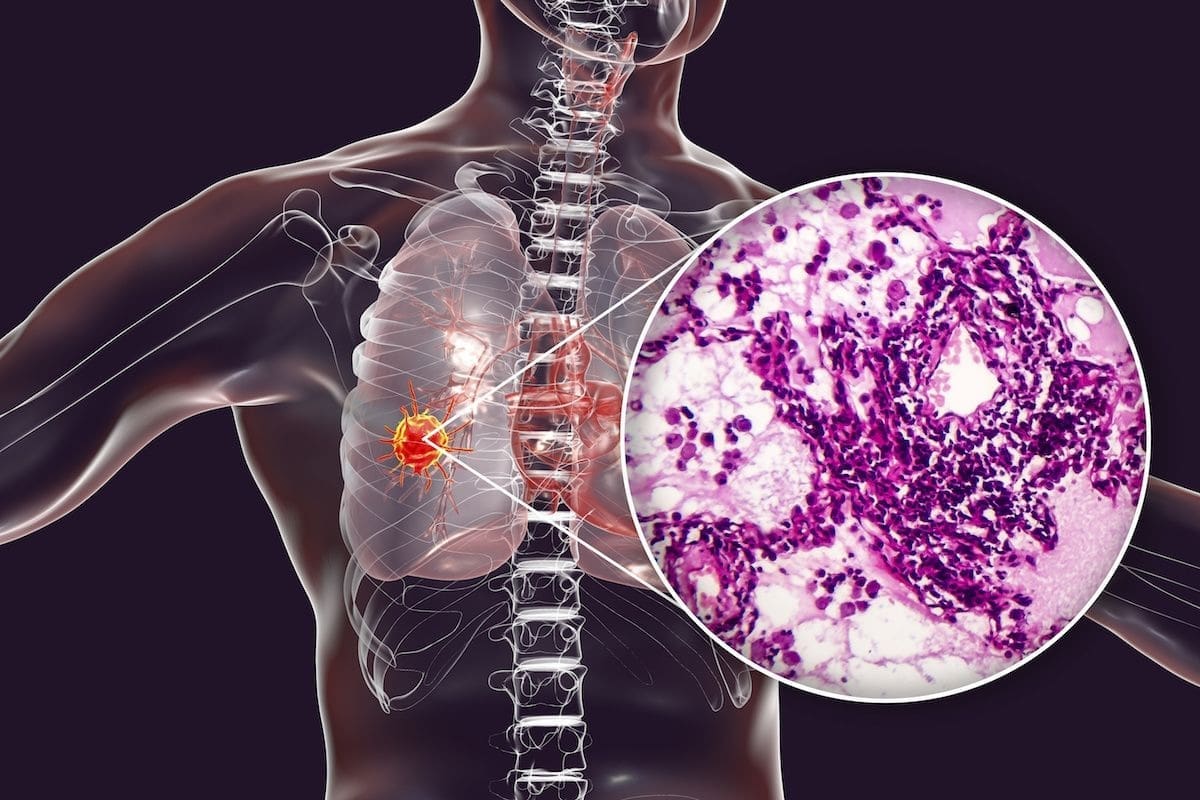

I got the results of the biopsy today. Good and not so good news. As expected, Dr Jarvie confirmed that I have non small cell carcinoma (NSCC, adenocarcinoma). No sign of metastases in other parts of the body. However, there is cancer activity in 2 nearby lymph nodes. Seeing another doctor (radiologist), Wednesday morning to line up treatment directed by the multidisciplinary team at Prince of Wales. Likely to be combo of targeted radio therapy and chemo therapy. Nothing definite yet. Surgery unlikely. May be clearer after the consult on Wednesday.